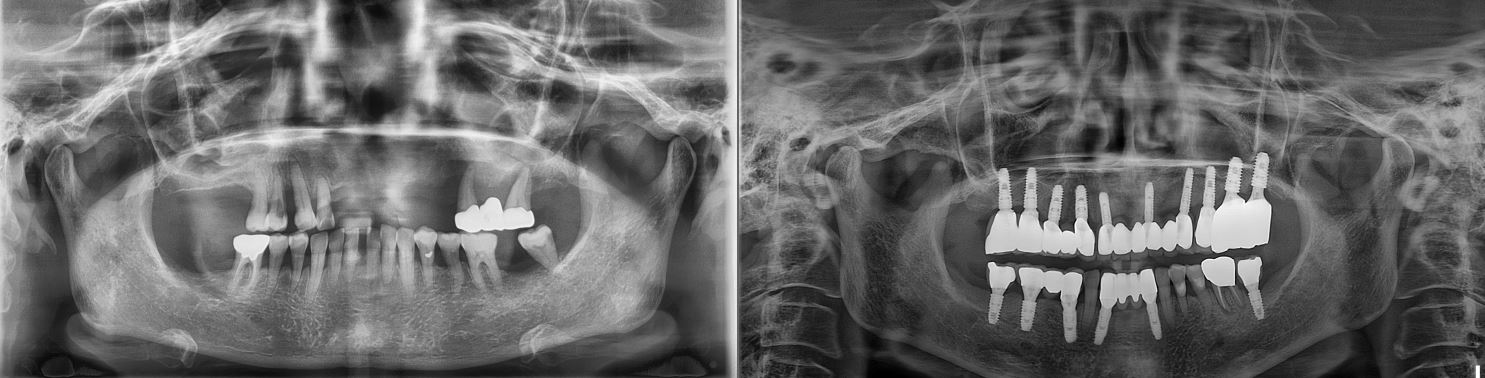

치료전후사진